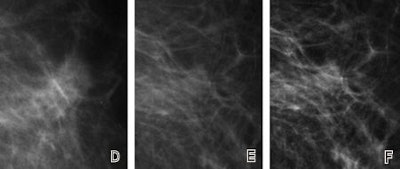

| Fatty breast depicted on (A, D, G) film-screen and (B, C, E, F, H, I) digital left mammograms obtained in 53-year-old woman. Cancerous areas are outlined in rectangles. (A-F) Mediolateral oblique and (G-I) craniocaudal views are shown. The cancer, a mass that proved to be an invasive ductal carcinoma, is much more apparent on the film-screen images than on the digital images, with visibility being greatest on the film-screen mediolateral oblique views. The difference in lesion visibility between the film-screen and digital mammograms is accentuated when the film-screen overview image (A) is compared with the digital overview image obtained by using the default image processing algorithm (B). Close-up views of cancerous areas outlined in A (D) and B (E) are shown. There is a slight improvement in the visibility of the lesion depicted at digital mammography performed by using the Premium View image processing software, as seen on digital mediolateral oblique overview (C), film-screen mediolateral oblique close-up view (D), and digital craniocaudal (I) images. |